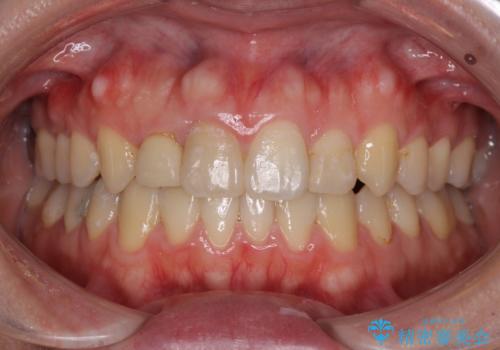

- 上下のデコボコと奥歯の咬みにくさを気にして来院された患者様です。

上顎骨の幅が下顎骨よりも小さいので、拡大装置により骨幅を広げて上下関係を改善し、その後インビザラインにて歯並びを整えることとしました。

上下の骨幅を改善したことで、スムーズに歯列矯正を行うことができました。

奥歯の咬み合わせを改善する必要があったため、治療は長期化しましたが、きっちりと仕上げることができました。